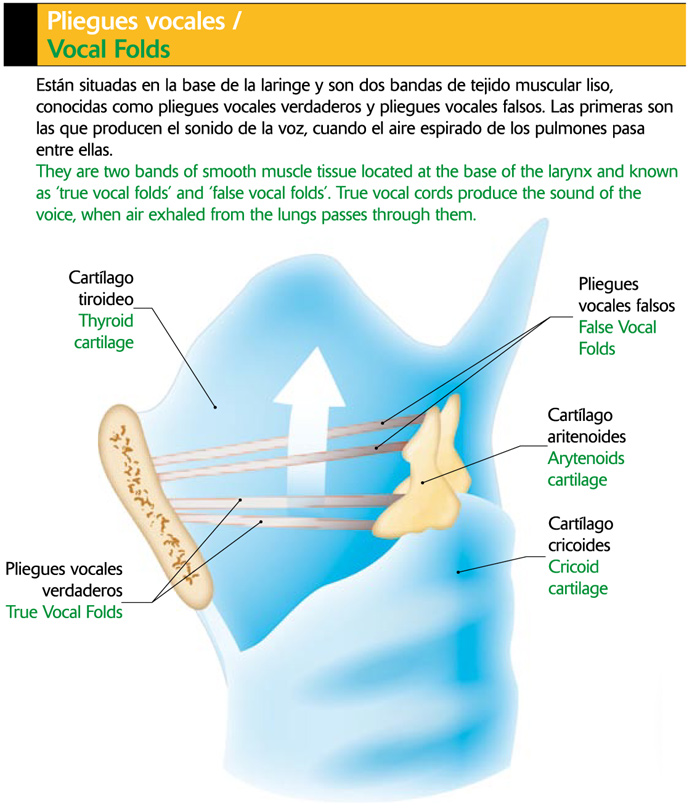

Laringe: Órgano complejo de este sistema que se ubica bajo la faringe y está constituido por cartílagos. Internamente contiene dos bandas fibrosas y delgadas llamadas Cuerdas vocales.

La laringe es responsable de la Fonación, determinada por las vibraciones de las cuerdas vocales y producida por el paso del aire lo que hace vibrar las cuerdas vocales. Todo esto es ayudado por los músculos que regulan el tono de voz, alargando o acortando las cuerdas.